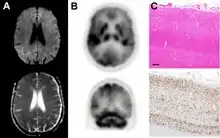

Histopathology

Spongiform change in CJD

Testing of tissue remains the most definitive way of confirming the diagnosis of CJD, although it must be recognized that even biopsy is not always conclusive.[51]

In one-third of people with sporadic CJD, deposits of "prion protein (scrapie)", PrPSc, can be found in the skeletal muscle and/or the spleen.[52] Diagnosis of vCJD can be supported by biopsy of the tonsils, which harbor significant amounts of PrPSc; however, biopsy of brain tissue is the definitive diagnostic test for all other forms of prion disease. Due to its invasiveness, biopsy will not be done if clinical suspicion is sufficiently high or low. A negative biopsy does not rule out CJD, since it may predominate in a specific part of the brain.[53]

The classic histologic appearance is spongiform change in the gray matter: the presence of many round vacuoles from one to 50 micrometers in the neuropil, in all six cortical layers in the cerebral cortex or with diffuse involvement of the cerebellar molecular layer.[54] These vacuoles appear glassy or eosinophilic and may coalesce. Neuronal loss and gliosis are also seen.[55] Plaques of amyloid-like material can be seen in the neocortex in some cases of CJD.[56]